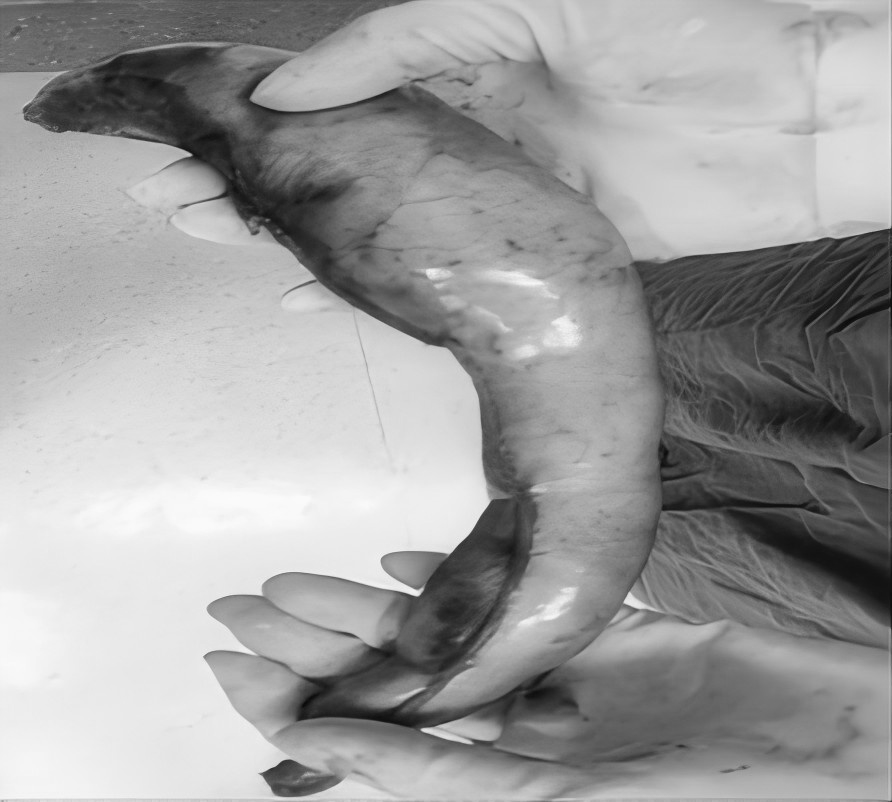

无数次立下减肥的誓言 尝试过五花八门的减肥方法 节食饿得头晕眼花 运动累得精疲力竭 但体重却像坐过山车 稍有松懈 就迅速反弹 别担心 或许减重手术 就是改变您体重的 关键契机 当前,肥胖已不仅仅是关乎外貌美观的问题,更像是一颗隐藏在身体里的定时炸弹,悄然引发各种慢性疾病。对于重度肥胖朋友来说,传统的饮食控制和运动往往收效甚微。而减重手术,为肥胖人群重获健康与自信带来了新的选择。 什么是减重手术? 减重手术,也被称为代谢手术,主要是对消化系统进行 “重塑”。目前,常见的手术方式有腹腔镜袖状胃切除术、腹腔镜胃旁路术及胃束带手术等。 比如,通过缩小胃容量,让您进食少量食物就有饱腹感,或者改变消化道结构,减少身体对营养的过度吸收。 胃旁路手术 袖状胃切除术 胃束带手术 减重手术真的有效果吗? 减重明显,告别肥胖 接受减重手术后,一般1到2年内,可以减掉超重体重的 60%-80%,让您告别肥胖困扰。 改善代谢,减少疾病 能够有效缓解Ⅱ型糖尿病、高血压、高血脂等肥胖相关疾病,让您重新拥有健康的身体状态。 减重手术,适合哪些人? 减重手术并非人人适用,需要经过严格、专业的术前评估。一般来讲,如果体重指数(BMI)≥30kg/m²,或者 体重指数(BMI)≥25 kg/m² 且合并有严重代谢性疾病,那么就可以将减重手术纳入考虑范围。 普外科专家简介 梁 跃 中共党员,普外科党支部书记、主任,主任医师 临床擅长:对普外科各类肿瘤手术具有丰富的临床经验。 毕业于遵义医学院,遵义市医学会小儿外科学分会常务委员,遵义市肛肠协会理事,遵义市医学会核医学分会(第二届)委员会委员;荣获第三期“黔医人才计划”优秀学员称号;主持市级课题1项,完成省级课题1项,在国内各类刊物上发表论文10余篇。 钱科洪 普外科副主任医师 临床擅长:从事普外科临床工作30余年,对各类普外科疾病的诊治、乳腺、甲状腺、胃十二指肠、结直肠等疾病及疑难杂症具有丰富的临床诊疗经验。 毕业于遵义医学院临床医疗系,2009年前往中山大学附属第一医院微创外科进修学习,在国内各专业期刊发表论文数篇。 贵州航天医院普外科简介 基本情况 贵州航天医院普外科成立于19世纪60年代,前身属于原航天部O61基地3417医院外一科,1998年更名为普外科,下设胃肠外科、肛肠外科2个亚专业科室,拥有专科设备和技术,是中国疝病专科联盟单位,贵州医科大学附属医院胃肠外科专科联盟单位。开放床位40张,配备医护人员21人。 专科特色 普外科致力于胃肠及肛肠疾病的外科临床诊治及科研,以腹腔镜微创外科技术为本,形成以快速康复治疗胃肿瘤、结直肠肿瘤、小肠肿瘤、直肠脱垂、肥胖病、急腹症、各类疝、痔、瘘等专科特色,同时注重胃肠疾病尤其是结直肠恶性肿瘤的基础研究和临床转化研究。 开展手术:腹腔镜下胃癌根治术,腹腔镜下袖状胃切除术,腹腔镜下胃肠道间质瘤切除术,腹腔镜下结、直肠癌根治术,胃癌、结直肠癌的精准治疗,腹腔镜下小儿疝气、成人疝修补术,腹腔镜下阑尾手术,内痔的硬化注射治疗及痔疮的微创治疗:ATH、PPH、TST,直肠脱垂的各种手术治疗,难治性伤口VSD技术,鼻胃肠管、肠梗阻导管置入术,肛肠术后间歇性导尿技术,并引进了中医适宜技术,也为各种化疗患者提供输液港安装,提高患者就医体验。 腹腔镜下腹股沟疝无张力修补术 腹腔镜下腹股沟疝 无张力修补术 腹股沟疝里金斯坦(Lichtenstein)手术 PPH微创术治疗环状混合痔 黏连性或炎性肠梗阻-肠梗阻导管 腹腔镜袖状胃切除 腹腔镜阑尾 切除术 腹腔镜阑尾肿瘤 切除术 腹腔镜下结肠癌根治术 诊疗范围 胃肿瘤、结直肠肿瘤、小肠肿瘤、肥胖症、各类急腹症、腹部外伤、腹壁疝、便秘、直肠脱垂、痔疮、肛瘘、肛裂等胃肠、肛肠外科疾病。 END